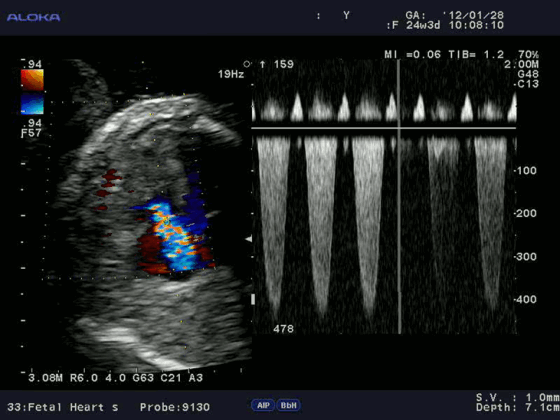

Для облегчения выявления турбулентного движения (завихрений) существует порог скорости, выше которого происходит изменение цвета (во многих аппаратах это зелены). «Мозаичный» узор на участке турбулентного потока позволяет легко установить регургитацию (смену направления движения), что помогает определить степень недостаточности клапанов.

Так, например, эхокардиография с допплерометрией и цветным допплеровским картированием (ЦДК), которая является сочетанием 2D и М-режимов с допплерометрией, очень полезна при оценке митрального стеноза. Первые два способа визуализации позволяют заподозрить кальцификацию клапана (аномальное движение его створок).

Допплерометрия демонстрирует при этой патологии повышенную скорость кровотока (признак сужения) и может быть использована для оценки «эффективной площади отверстия» (степени выраженности стеноза).